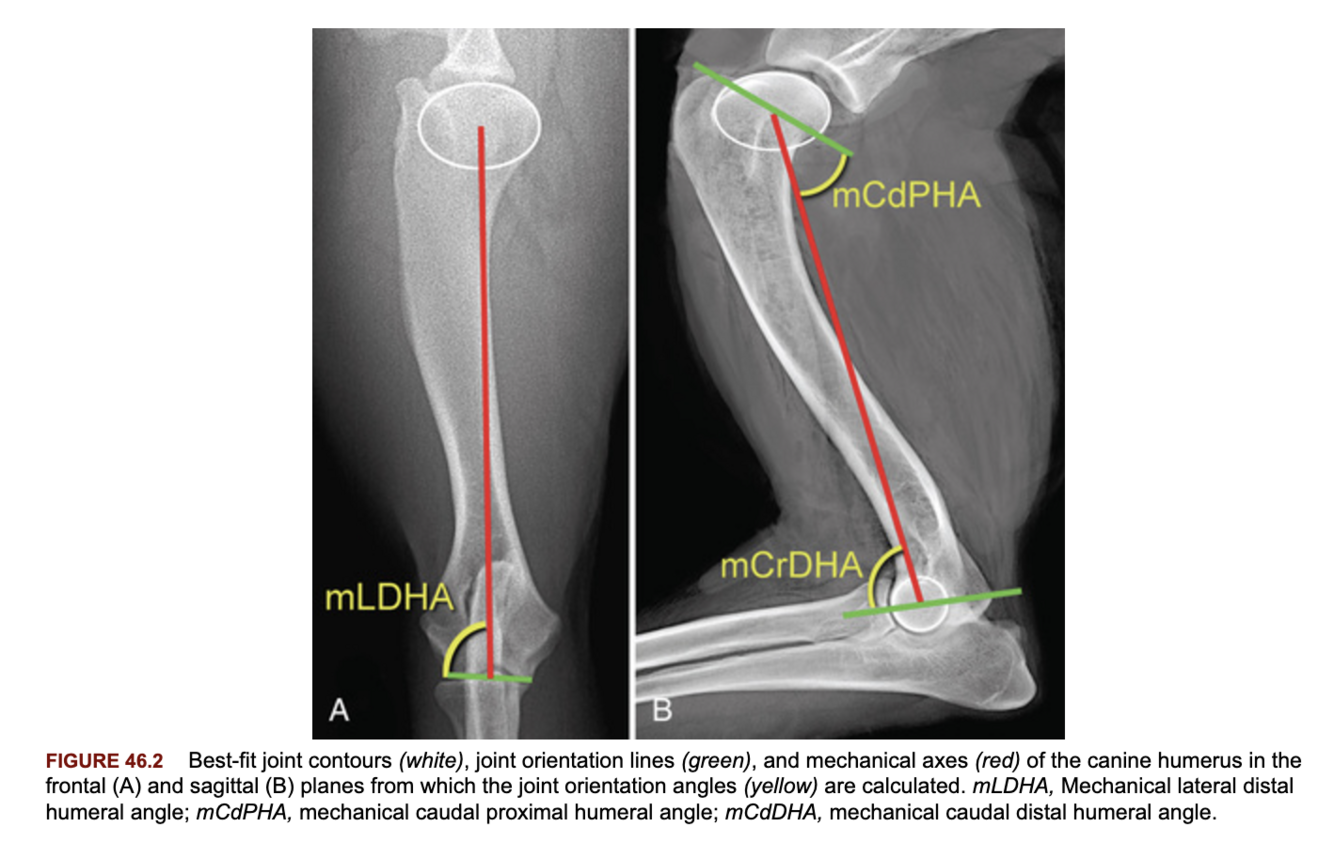

What is the difference between the anatomic and mechanical axes of the bone?

A

Anatomic: a line that passes through the center (or mid-diaphysis) of the bone in the frontal or sagittal plane.

Mechanical: a line that passes through the center of the proximal and distal joints (may be more clinically useful than the anatomic axis for sigmoidal bones such as the tibia, humerus).

Describe how the joint orientation lines and anatomic axis of the femur are determined?

Frontal plane: joint line distally, center of the femoral head to the proximal greater trochanter proximally.

Anatomic axis: determined by a line that connects points measured 33 and 50% distal to a point at the proximal margin of the femoral neck.